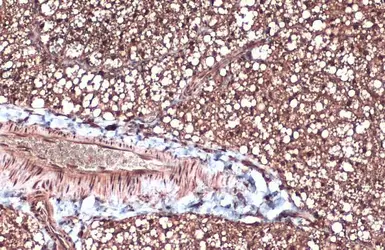

Anti-FABP4 antibody [N3C3] used in IHC (Paraffin sections) (IHC-P). GTX116036

GTX116036 IHC-P Image

FABP4 antibody [N3C3] detects FABP4 protein at cytoplasm and nucleus by immunohistochemical analysis.

Sample: Paraffin-embedded mouse brown adipocyte.

FABP4 stained by FABP4 antibody [N3C3] (GTX116036) diluted at 1:500.

Antigen Retrieval: Citrate buffer, pH 6.0, 15 min